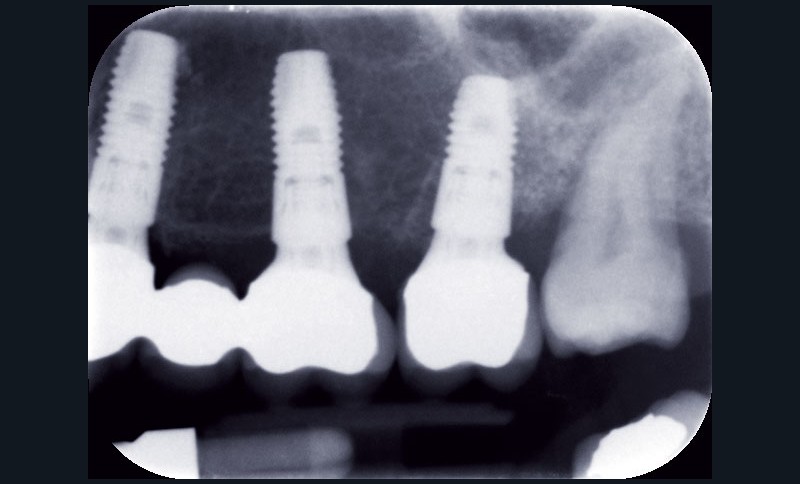

Au maxillaire, 3 implants Astra Tech Implant EV (Dentsply) sont posés en un temps chirurgical. Une empreinte pick-up sera réalisée après 4 mois de cicatrisation.

Une fois les transferts pick-up EV® transvissés, le porte-empreinte Tray, fenestré en regard des transferts, est chargé de matériau monophase Impregum™ Penta™ Soft (3M ESPE). Du matériau est déposé autour des transferts à l’aide d’une seringue. Après dévissage des transferts, ces derniers sont emportés dans l’empreinte et les analogues d’implants sont transvissés.

Une fois les transferts pick-up EV® transvissés, le porte-empreinte Tray, fenestré en regard des transferts, est chargé de matériau monophase Impregum™ Penta™ Soft (3M ESPE). Du matériau est déposé autour des transferts à l’aide d’une seringue. Après dévissage des transferts, ces derniers sont emportés dans l’empreinte et les analogues d’implants sont transvissés.

Une fois les transferts pick-up EV® transvissés, le porte-empreinte Tray, fenestré en regard des transferts, est chargé de matériau monophase Impregum™ Penta™ Soft (3M ESPE). Du matériau est déposé autour des transferts à l’aide d’une seringue. Après dévissage des transferts, ces derniers sont emportés dans l’empreinte et les analogues d’implants sont transvissés.

Une fois les transferts pick-up EV® transvissés, le porte-empreinte Tray, fenestré en regard des transferts, est chargé de matériau monophase Impregum™ Penta™ Soft (3M ESPE). Du matériau est déposé autour des transferts à l’aide d’une seringue. Après dévissage des transferts, ces derniers sont emportés dans l’empreinte et les analogues d’implants sont transvissés.

Une fois les transferts pick-up EV® transvissés, le porte-empreinte Tray, fenestré en regard des transferts, est chargé de matériau monophase Impregum™ Penta™ Soft (3M ESPE). Du matériau est déposé autour des transferts à l’aide d’une seringue. Après dévissage des transferts, ces derniers sont emportés dans l’empreinte et les analogues d’implants sont transvissés.

Le modèle de travail est fabriqué au laboratoire, des piliers CFAO Atlantis™ sont réalisés en fonction du bridge antagoniste transitoire.

Le modèle de travail est fabriqué au laboratoire, des piliers CFAO Atlantis™ sont réalisés en fonction du bridge antagoniste transitoire.

Le bridge 24-26 céramométallique et la couronne unitaire sur 27 sont réalisés. Les piliers CFAO sont transvissés sur les implants, puis les éléments céramo-métalliques sont posés. Le résultat montre un parfait respect du projet prothétique en fonction de la courbe occlusale obtenue avec le bridge transitoire réalisé avec le ProtempTM 4 et une adaptation parfaite.

Le bridge 24-26 céramométallique et la couronne unitaire sur 27 sont réalisés. Les piliers CFAO sont transvissés sur les implants, puis les éléments céramo-métalliques sont posés. Le résultat montre un parfait respect du projet prothétique en fonction de la courbe occlusale obtenue avec le bridge transitoire réalisé avec le ProtempTM 4 et une adaptation parfaite.

Le bridge 24-26 céramométallique et la couronne unitaire sur 27 sont réalisés. Les piliers CFAO sont transvissés sur les implants, puis les éléments céramo-métalliques sont posés. Le résultat montre un parfait respect du projet prothétique en fonction de la courbe occlusale obtenue avec le bridge transitoire réalisé avec le ProtempTM 4 et une adaptation parfaite.

Le bridge 24-26 céramométallique et la couronne unitaire sur 27 sont réalisés. Les piliers CFAO sont transvissés sur les implants, puis les éléments céramo-métalliques sont posés. Le résultat montre un parfait respect du projet prothétique en fonction de la courbe occlusale obtenue avec le bridge transitoire réalisé avec le ProtempTM 4 et une adaptation parfaite.

Le bridge 24-26 céramométallique et la couronne unitaire sur 27 sont réalisés. Les piliers CFAO sont transvissés sur les implants, puis les éléments céramo-métalliques sont posés. Le résultat montre un parfait respect du projet prothétique en fonction de la courbe occlusale obtenue avec le bridge transitoire réalisé avec le ProtempTM 4 et une adaptation parfaite.